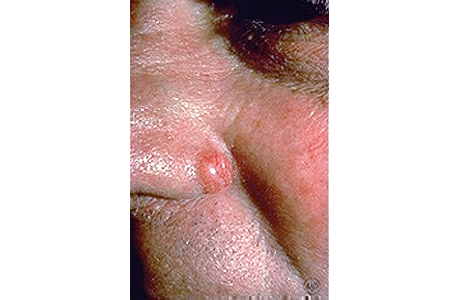

3. Warning sign: A sore that doesn't heal (or heals and returns) and may bleed, ooze, or crust over

Can be mistaken for: Sore or pimple

A sore that doesn't heal, or heals and returns

This patient mistook the BCC on his nose for a non-healing pimple.

Close-up of basal cell carcinoma on a patient's nose